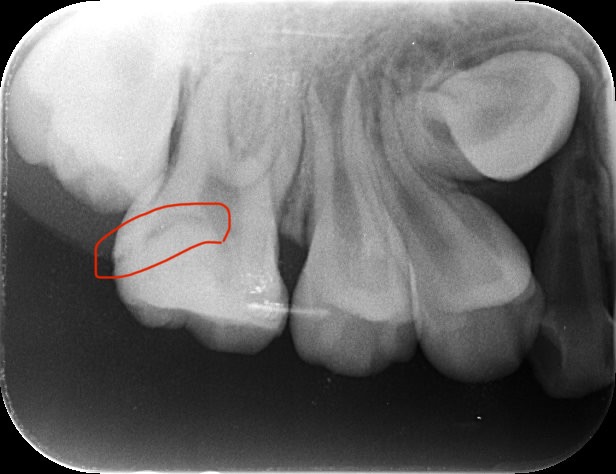

前歯がこんな感じになっていたら、

それは、虫歯です。

それでも今回のように、

実際に虫歯で穴があいてしまったら、

歯医者で虫歯治療をしなければなりません。

治療後の写真です。

虫歯を削って、白い詰め物で埋めました。

虫歯が小さければ、痛みもなく、麻酔なしで処置することも可能です。

←治療前

←治療前